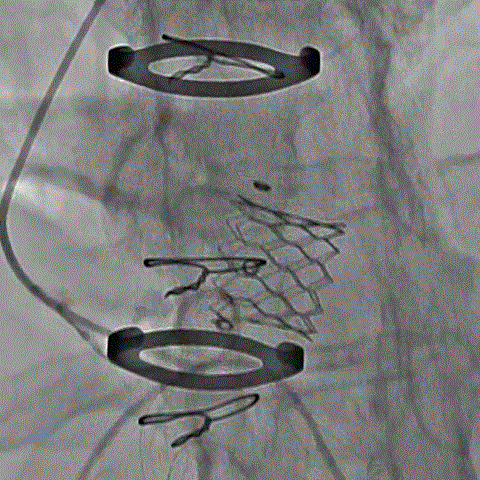

球扩瓣膜 蓄势待发

佰仁医疗Renato介入瓣中瓣系统,采用全球主流的球扩式设计,瓣架高度与外科瓣类同、径向支撑力强,输送安全、定位精准,易于释放,适合于不同瓣位及不同入路的瓣中瓣手术。该瓣膜的设计与工艺实现了以本企业成熟的外科牛心包瓣同样的启闭模式与血流动力学特性,特别是加速疲劳测试验证了其与外科牛瓣相同的耐久性,采用经长期临床验证的抗钙化改性处理的牛心包为瓣叶材料,使该产品顺利通过全性能注册检验和动物实验验证,目前已启动正式多中心临床试验。该临床试验正面向社会招募患者,为更多类似需要救治的危重患者提供救治机会。